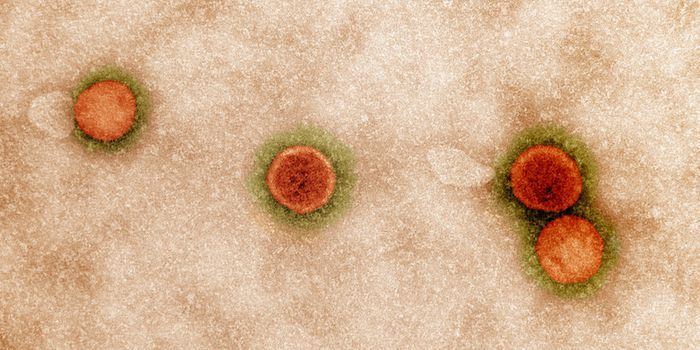

APR 27, 2025MicrobiologyThe SARS-CoV-2 virus that causes COVID-19 emerged to cause millions of deaths and sicken billions of people...

MAR 16, 2025Cell & Molecular BiologyScientists have learned more about how SARS-CoV-2 infections, which cause COVID-19, can ruin the ability of immune cells ...